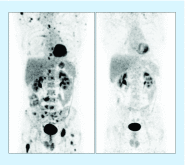

The contribution of nuclear medicine to management of melanoma patients is increasing. In intermediate-thickness N0 melanomas, lymphoscintigraphy provides a roadmap for sentinel node biopsy. With the introduction of single-photon emission computed tomography images with integrated computed tomography (SPECT/CT), 3D anatomic environments for accurate surgical planning are now possible. Sentinel node identification in intricate anatomical areas (pelvic cavity, head/neck) has been improved using hybrid radioactive/fluorescent tracers, preoperative lymphoscintigraphy and SPECT/CT together with modern intraoperative portable imaging technologies for surgical navigation (free-hand SPECT, portable gamma cameras). Furthermore, PET/CT today provides 3D roadmaps to resect 18F-fluorodeoxyglucose-avid melanoma lesions. Simultaneously, in advanced-stage melanoma and recurrences, 18F-fluorodeoxyglucose-PET/CT is useful in clinical staging and treatment decision as well as in the evaluation of therapy response. In this article, we review new insights and recent nuclear medicine advances in the management of melanoma patients.